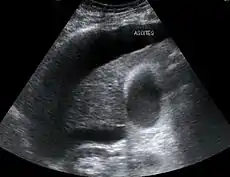

Os critérios maiores incluem a doença de fígado aguda ou crônica, com hipertensão portal; insuficiência renal; ausência de choque, infecção, tratamento recente com medicamentos que afetam a função renal (nefrotoxinas) e perdas de fluido; ausência de melhora sustentada da função renal apesar do tratamento com 1,5 litros de solução intravenosa salina; ausência de proteinúria (proteína na urina); e, ausência de doença renal ou obstrução ao fluxo renal visto numa ultrassonografia.[3]

Diferente da síndrome hepatorrenal do tipo 1, que tem uma evolução rápida, a do tipo 2 tem início e progressão bem mais lentos. Ela é definida por um aumento no nível de creatinina sérica em mais de 133 mmol/L (1,5 mg/dL) ou por uma depuração de creatinina inferior a 40 mL/min, e um sódio urinário menor que 10 mmol/L.[6] Ela também possui um prognóstico pobre, com uma sobrevida média de cerca de seis meses, a menos que seja feito um transplante de fígado no indivíduo afetado. A SHR do tipo 2 parece fazer parte de um espectro de doenças associadas com o aumento da pressão na circulação da veia porta, que se manifesta clinicamente com o acúmulo de líquido no abdome, a ascite. O espectro continua com uma ascite refratária a diuréticos, quando os rins não mais conseguem excretar sódio suficiente para eliminar líquido mesmo com o uso de medicamentos diuréticos. Muitos pacientes com a SHR do tipo 2 tem uma ascite com essas características antes de desenvolverem a deterioração da função renal.[7]

Os dois tipos da síndrome hepatorrenal partilham três fenômenos principais: função do fígado alterada, anormalidades na circulação e insuficiência renal. Já que esses fenômenos não produzem de fato sintomas até o fim do curso da doença, os indivíduos que sofrem com esta síndrome geralmente são diagnosticados com base em exames laboratoriais alterados. A maioria das pessoas que desenvolvem SHR têm cirrose e por isso podem ter os mesmos sinais e sintomas desta doença, como icterícia, alteração do estado mental, nutrição prejudicada e a presença de ascite.[2] Especificamente, o surgimento de ascite, que é resistente ao uso de medicamentos diuréticos, é característica do tipo 2 de SHR. A oligúria, que significa uma diminuição no volume de urina, pode ocorrer como consequência da insuficiência renal. Todavia, alguns indivíduos com SHR continuam a produzir urina normalmente.[3] Como estes sintomas podem não aparecer, não são incluídos como critérios maiores ou menores para o diagnóstico desta condição. Invés disso, a doença é diagnosticada no indivíduo a partir de resultados de testes laboratoriais para a exclusão de outras causas.[3]